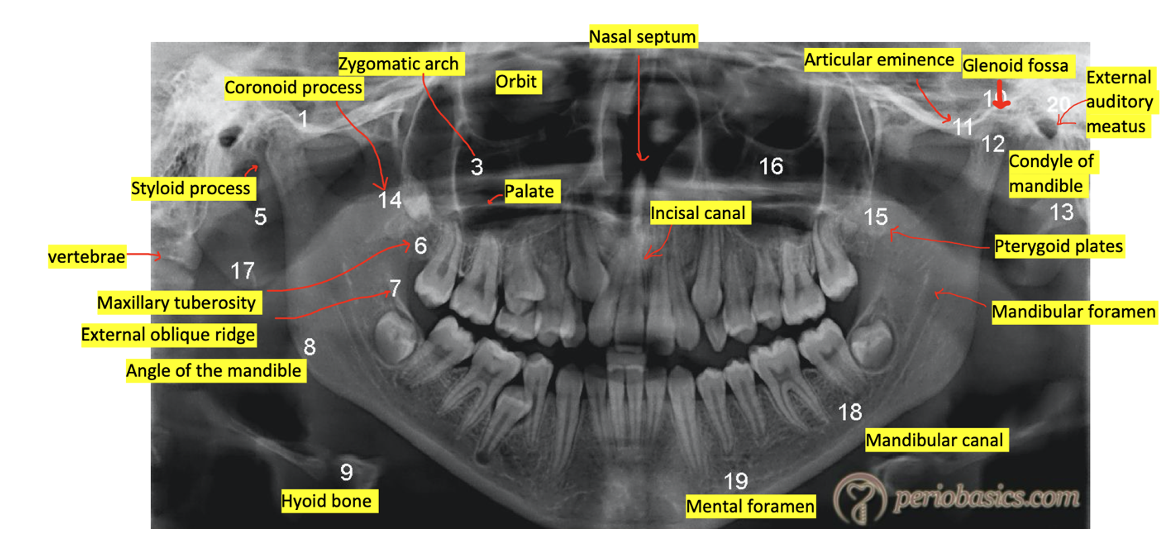

(OPT provided)

Identify the;

* Condyle

* Hard palate

* Zygomatic buttress

* Styloid process

* Soft palate

* Hyoid bone

* Nasal septum

* Ear lobe

* Bite peg

* Ghost image of opposite lower mandible